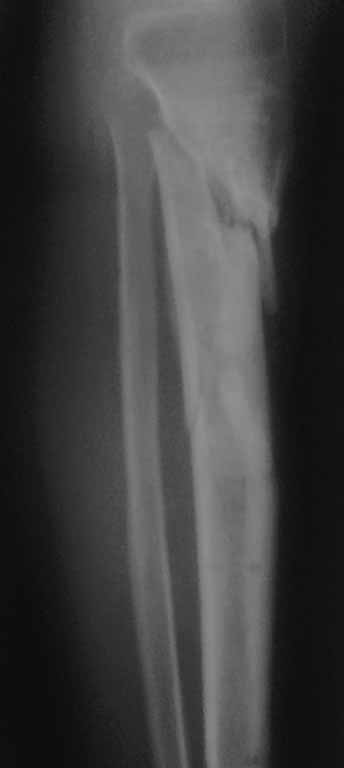

Важны мнения опытных докторов владеющих интрамедуллярным остеосинтезом. Пациент 50 лет.В анамнезе з/оскольч.перелом в/з-с/3 б/б кости. Был в АВФ 9 мес, демонтирован по его словам по поводу спицевой инфекции.также был со слов вскрыт гнойник на передней поверхности голени в зоне ложняка. на данный момент клинически: патол.подвижность в в/з голени и заживающая рана 0,2*4см по передней поверхности голени в зоне ложняка с скудно-умеренным серозным отделяемым( скорее вне зоны проведения спиц). Подвижность -умереннная. Трофических и сосудистых нарушений можно сказать нет. Сгибание в коленном суставе возможно без насилия ок. 50град. Вопрос - как делать? Нам предстваляется два пути: 1.Не дожидаясь заживления раны о/с АВФ,с открыванием ложняка: почистить его+ остеотомия малобрецовой ближе к н/3-с/3 границе. 2.перевязывать рану, после заживления подождать недельки две. Паралельно разрешить приступать на конечность. 2.1Если гной будет то см.вариант1.

2.2 Если гноя нет возможна ли установка штифта ???Т.к. 1) верхнее плечо перелома короткое 2) Риск сломать осколки при штифтовании в связи с разрушением эндостальной мозоли 3) угроза инфицирования, конечно если нагноится то опять см. вар.1. Есть конечно варианты штифта с антибиот покрытием, но это не панацея. У кого был такой опыт поделитесь пожалуйста наблюдениями( лучше с проиллюстрированными R)

Жаль, что нет фасной проекции. Перелом на 2 уровнях, есть искривление костно-мозгового канала. Проксимальный отломок короткий. Вывод: лучше не штифтовать.

3.Перелом на 2 уровнях, есть искривление костно-мозгового канала. Проксимальный отломок короткий.